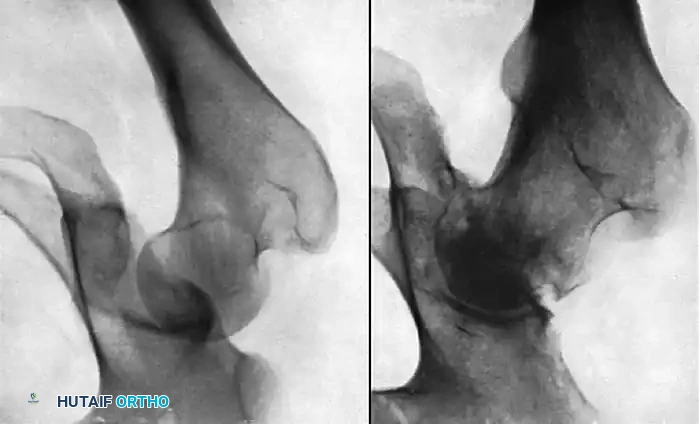

Fig. 57-13 A, Posterior dislocation of the hip. B, Osteonecrosis of the femoral head 8 months after closed reduction. Note the profound subchondral sclerosis, narrowed joint space, and early femoral head collapse.